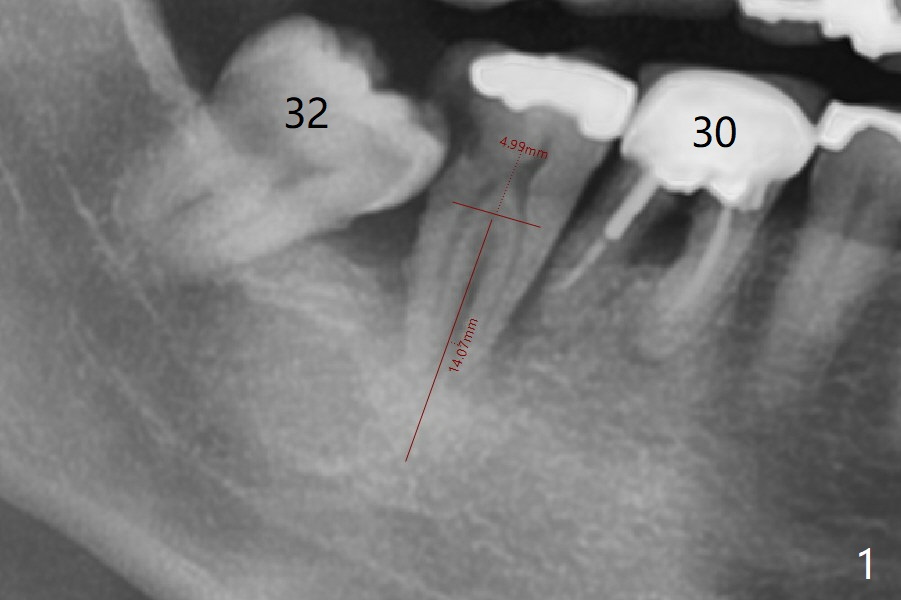

A 56-year-old man has complicated infection in the lower right posterior region (Fig.1). It appears that all of the molars need extraction. To alleviate financial burden, the teeth #31 and 32 will be first extracted with immediate implant at #31 (Fig.2).